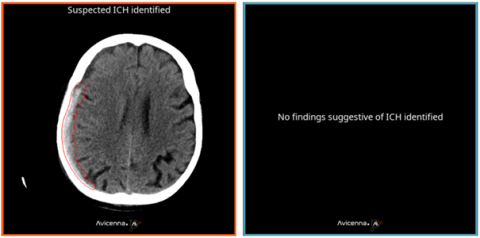

L’hémorragie intracrânienne (HIC) représente un enjeu majeur de santé publique en raison de sa mortalité précoce élevée, nécessitant un diagnostic rapide par scanner cérébral sans injection. L’intelligence artificielle s’intègre progressivement en radiologie, notamment pour la détection et le triage des urgences neurovasculaires, mais ses performances peuvent diminuer en validation externe, soulignant la nécessité d’évaluations indépendantes. De nombreux outils dédiés à la détection automatisée des HIC rapportent des performances élevées, mais restent souvent limités par des biais méthodologiques (design rétrospectif, exclusion des diagnostics différentiels, vérité terrain mono-lecteur), réduisant leur applicabilité clinique. Dans ce contexte, cette étude a évalué les performances du logiciel de triage des HIC, CINA-ICH v1.0.8 (Avicenna.ai) (voir image 1), à partir d’une cohorte rétrospective bicentrique originale et d’une cohorte prospective monocentrique, afin de se rapprocher des conditions de pratique clinique réelle.

Image1 clotide ruesh.png

Image 1: Images générées par CINA-ICH (à gauche, quand résultat positif, à droit quand négatif)